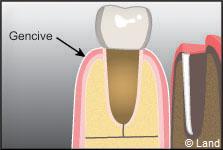

La dent est composée d’une couronne et d’une ou plusieurs racines incluses dans l’os alvéolaire.

La dent est articulée avec l’os alvéolaire par le ligament alvéolo-dentaire. Il agit comme un amortisseur entre la dent et l’os. Le cément est une couche mince recouvrant la racine et/ou les ligaments parodontaux rattachant la racine à l’os.